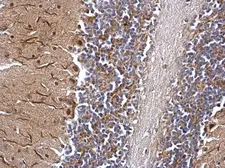

Images